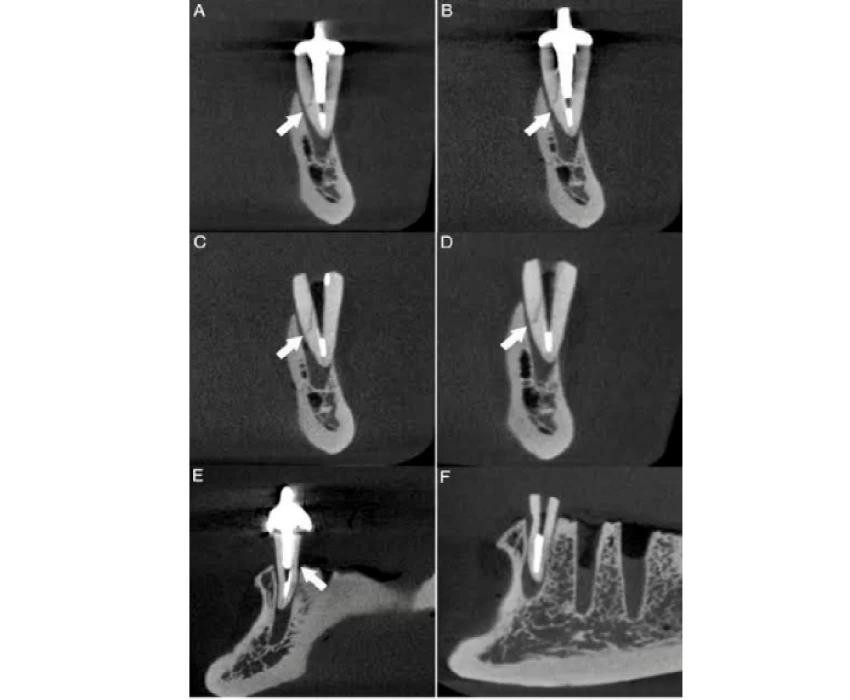

Over the past three decades, dentistry as a whole has made enormous strides. With these developments, it is now essentials to use more accurate diagnostic tools, particularly imaging techniques, keeping that in mind Dr. Tanmay has adapted modern dentistry in the form of advanced imaging methods including computed tomography, cone beam compute tomography, magnetic resonance imaging, and ultrasound along with all the conventional techniques.

The transition from analogue to digital radiography has simplified and sped up the procedure while also making image modification, storage, and retrieval simpler. The intricate craniofacial structures are now easier to examine thanks to 3-D imaging.

He has a wealth of knowledge in the interpretation of CBCT scans and has numerous papers and related research to his name.